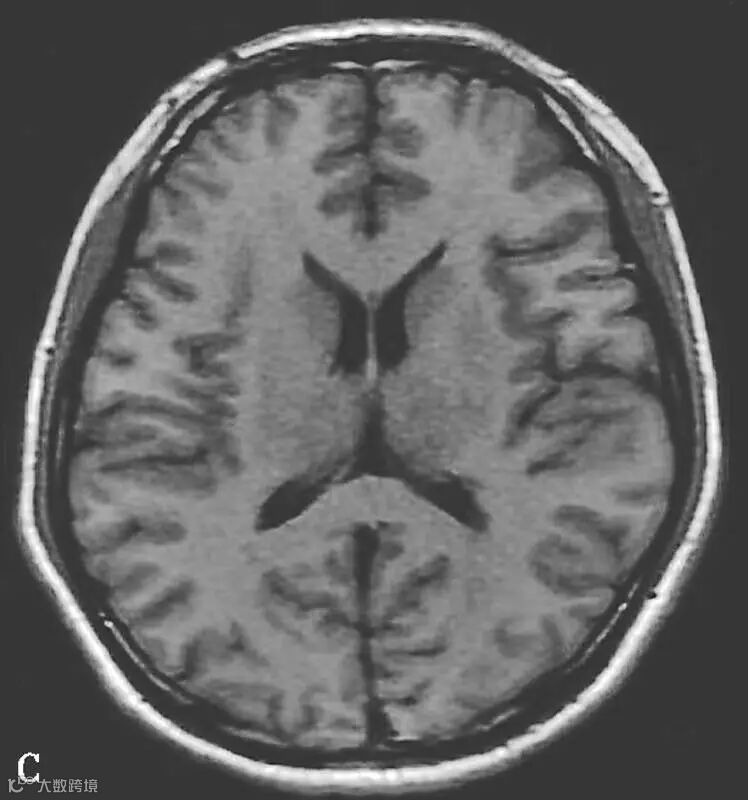

图6-11-2 弥漫性轴索损伤

男,36岁,外伤后2天。A~J(A、B.T2WI,C、D.T1WI,E、F.T2WI-FLAIR,G、H.DWI,I、J.ADC图):双侧额叶、半卵圆中心及胼胝体压部可见多发斑点状等T1稍长T2信号,边缘不清,FLAIR及DWI呈高信号,ADC图病灶信号减低 。